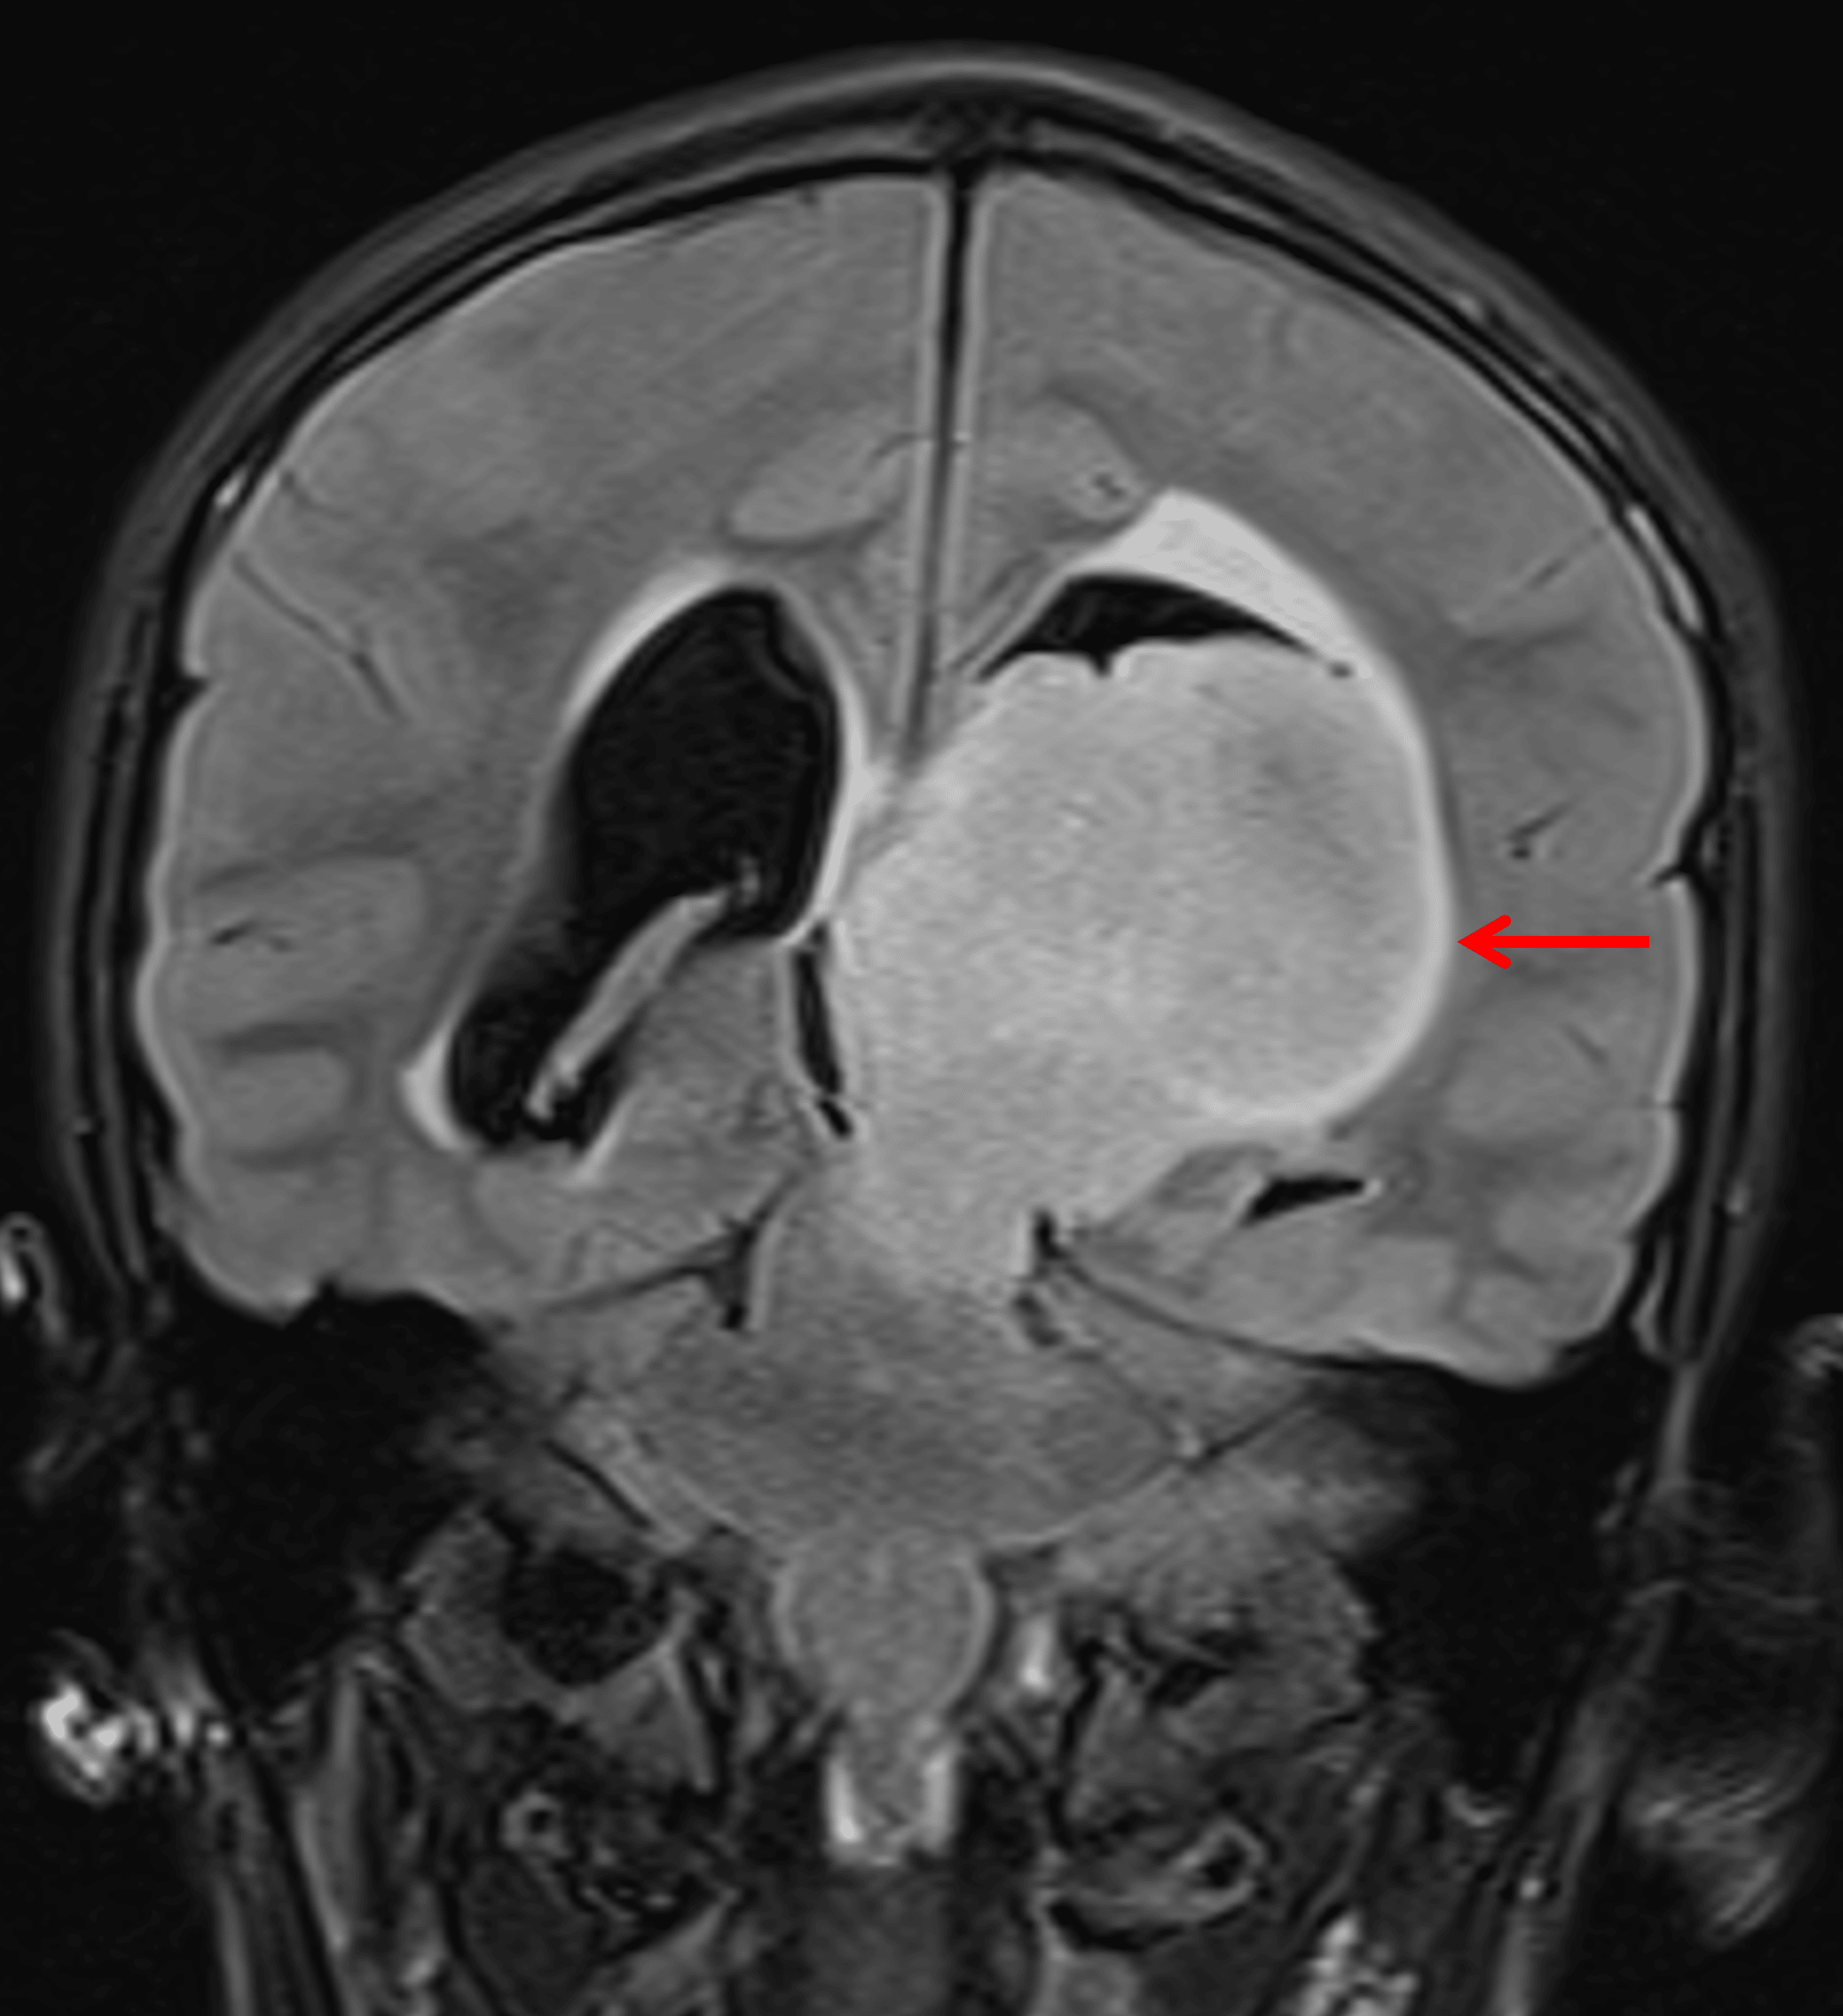

- Areas of internal restricted diffusion, particularly in the inferior and anterosuperior aspects of the mass

Area of relatively low ADC in the anterosuperior portion of the mass (red arrow), likely correlating with an area of higher cellularity.